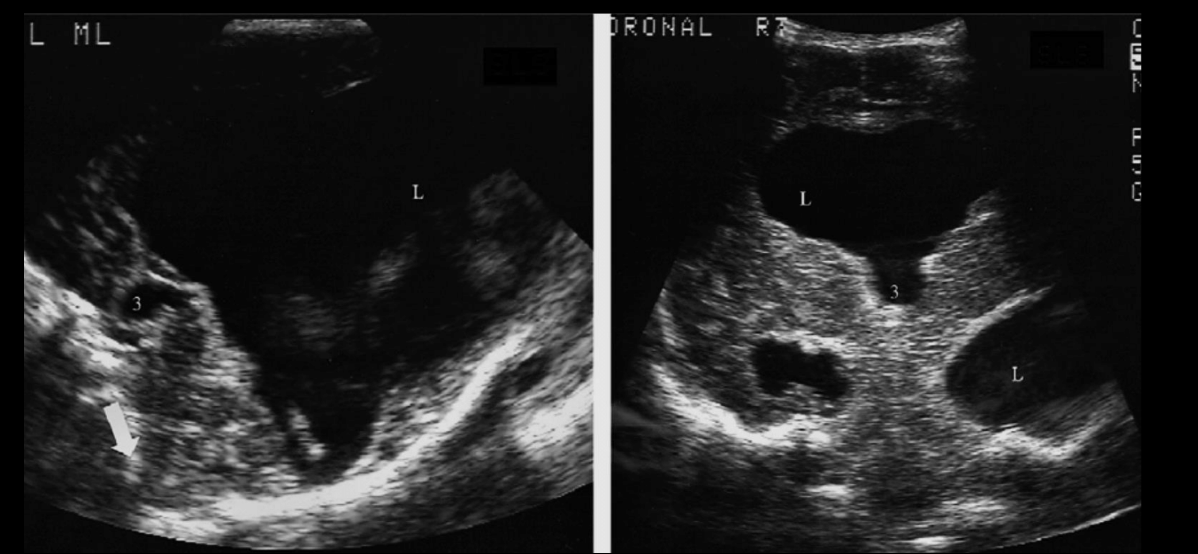

Imagen

Se puede: RM, TC, USG

Se detecta en US in utero

US transfontanelar